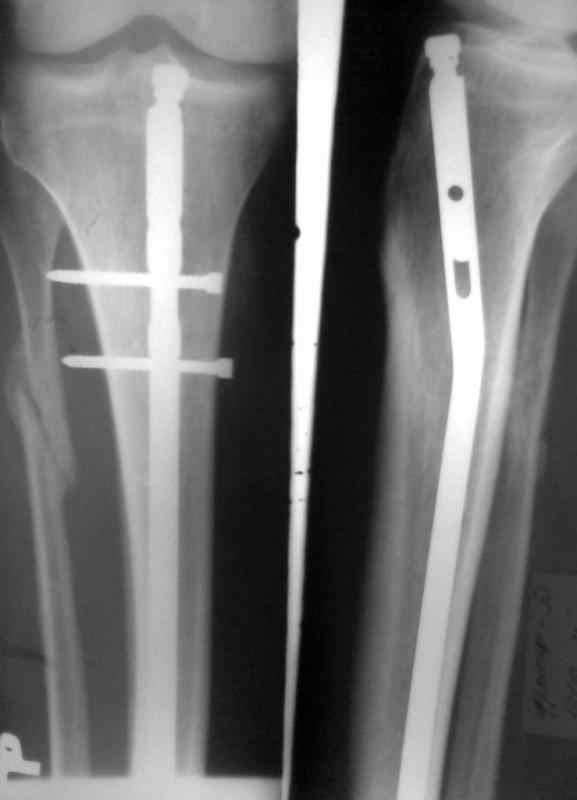

Сломан дистальный блокирующий винт Больному произведено ОМС перелома голени блокирующим стежнем 2 мес. назад. Через 1 мес больной начал наступать на ногу. В результате такая картина. Удален сломаный конец винта.Интересует вопрос о дальнейшей тактике лечения. Кто может посоветовать как дальше поступить. Оставить все как есть и приступать на ногу, провести замену стержня на другой или поступить как-то иначе. Спасибо за советы и предложения

снимки в приложении

Мое мнение - есть хорошая мозоль, и ось конечности весьма неплоха. Я бы оставил все как есть и рекомендовал бы больному на всякий случай повременить с нагрузкой на ногу еще на пару месяцев .

Конечно, изначально было бы лучше гвоздь взять на 2-4 см длиннее ( скорее на 4) и заблокировать его 2-3 шурупами, но, что сделано - то сделано